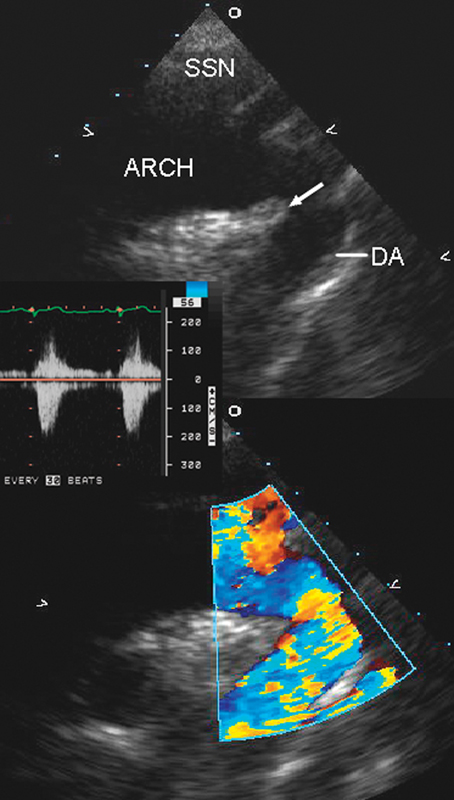

فحوصات تشخيصية لبعض امراض القلب والشرايين التاجية